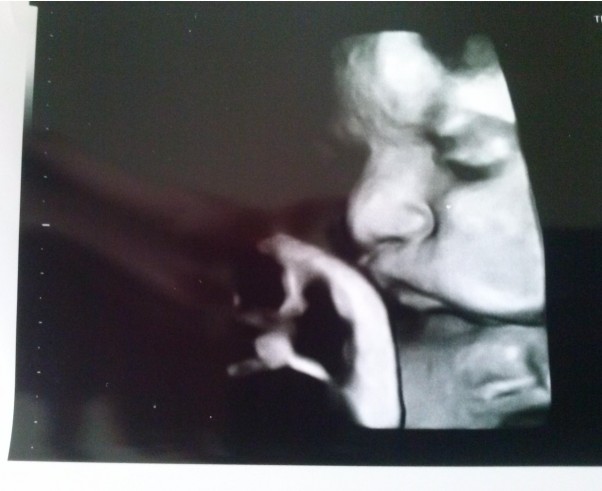

38. tydzień - bobas nabrał ciałka. Ma między 3000, a 3400 gram i tylko czekać aż zechce się nam pokazać. Na razie fotka z dzisiejszego USG.